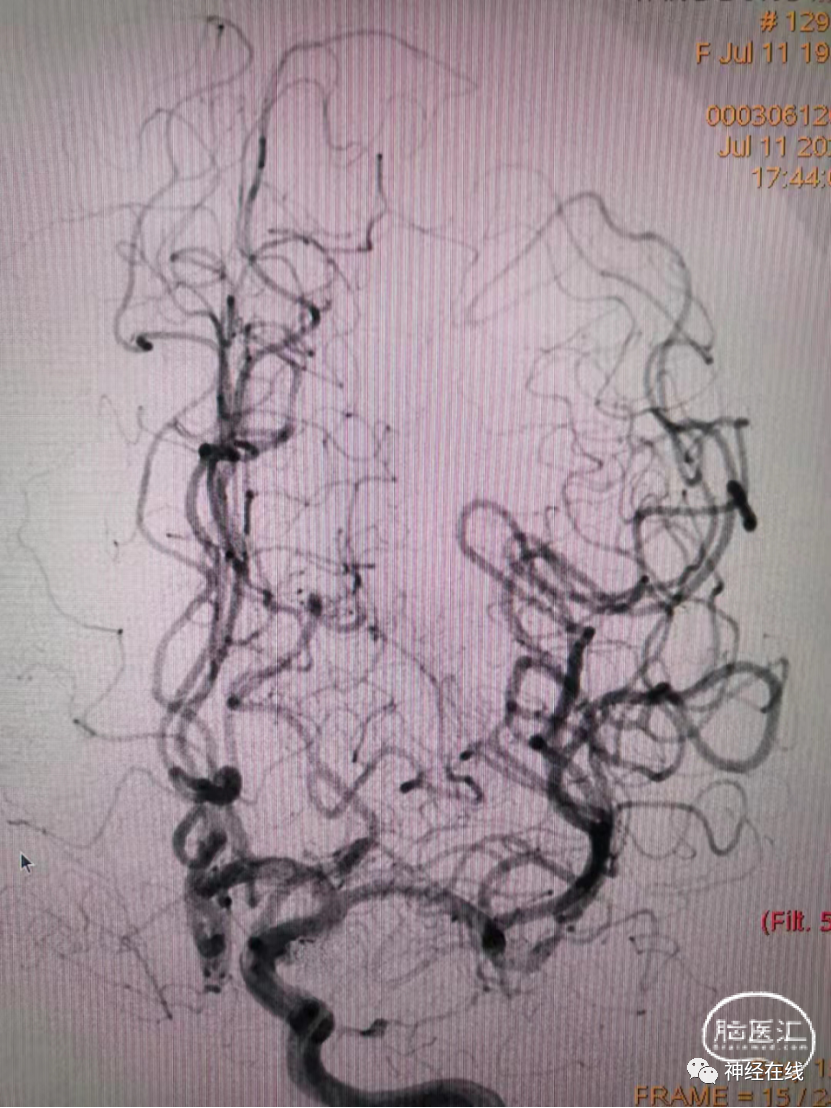

长条状破裂后交通动脉瘤弹簧圈栓塞病例